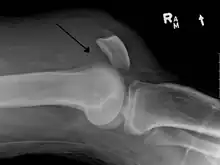

![]() | |

| An x-ray demonstrating quadriceps tendon rupture. Note the abnormal angle of the patella and soft-tissue swelling marked by the arrow. | |